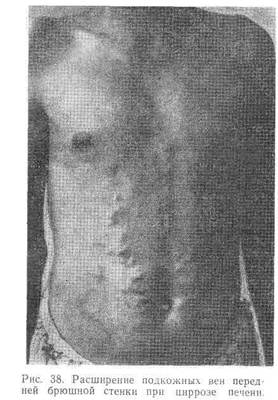

При выраженной портальной гипертензии на коже живота, вначале на боковых поверхностях, обнаруживается расширение подкожных вен (Влголова медузыВ»). Нередко наблюдаются расширение прямокишечных вен, иногда тяжелые кровотечения из них, а также варикозное расширение нижних вен пищевода, реже тАФ в области кардиального отдела желудка, при разрыве которых могут возникнуть угрожающие для жизни больного кровотечения, в большинстве случаев в виде кровавой рвоты.

При физическом обследовании брюшной полости в ряде случаев отмечается метеоризм, часто расширение подкожных вен живота (рис. 38). Как правило, в начальной стадии печень увеличенная, плотная, с заостренным краем; часто прощупывается увеличенная селезенка.